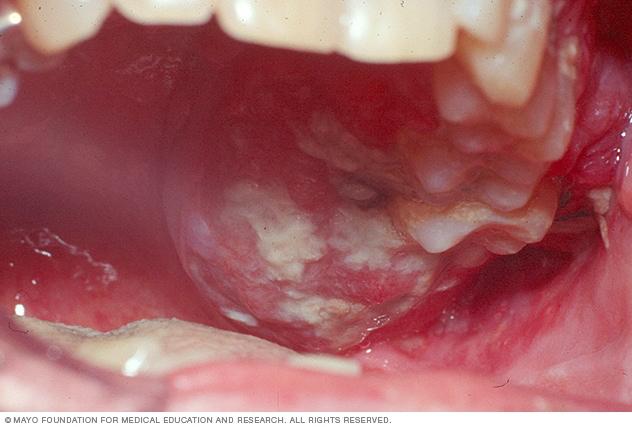

Oral Cancer: A Medical Insight into Mouth Tumors